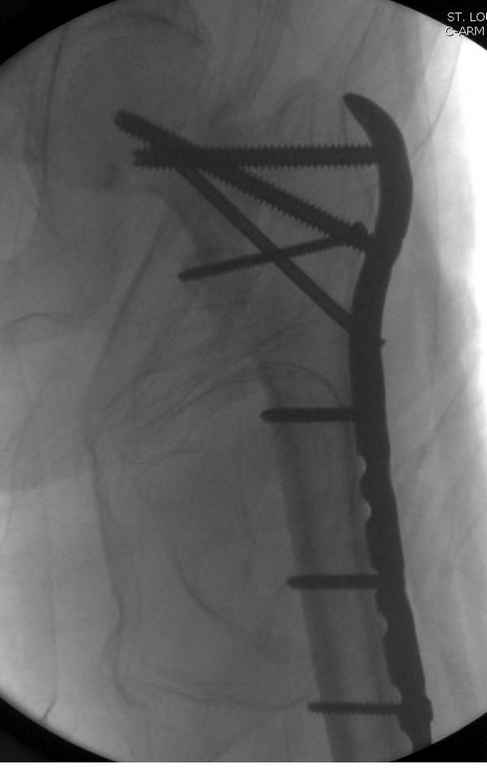

Здесь пара похожих случаев.

Djoldas Kuldjanov, MD

Department of Orthopedic Surgery

St. Louis University Medical Center

Увожаемый коллега,мое мнение:фиксация и\медул.блок. стержнем Gamma-long "STRYKER". Вероятно, закрыто сделать полностью может не получится. Откроетесь на 6-8 см. для репозиции промежуточного фрагмента, но только после установки стержня. Удачи!!!